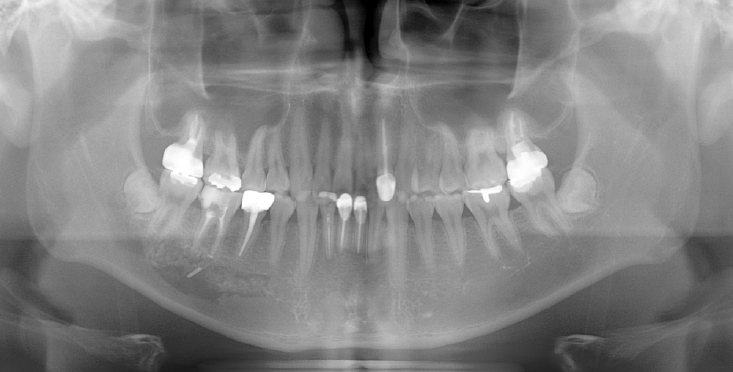

A 41-year-old female reported persistent numbness in the right lower lip and chin following endodontic treatment of the mandibular right second molar (#47). A panoramic radiograph and CBCT revealed extrusion of Calcipex II into the IAN (Fig. 3). She declined surgical intervention and was treated conservatively with mecobalamin and gabapentin. Serial follow-ups at one and three months showed no clinical improvement.